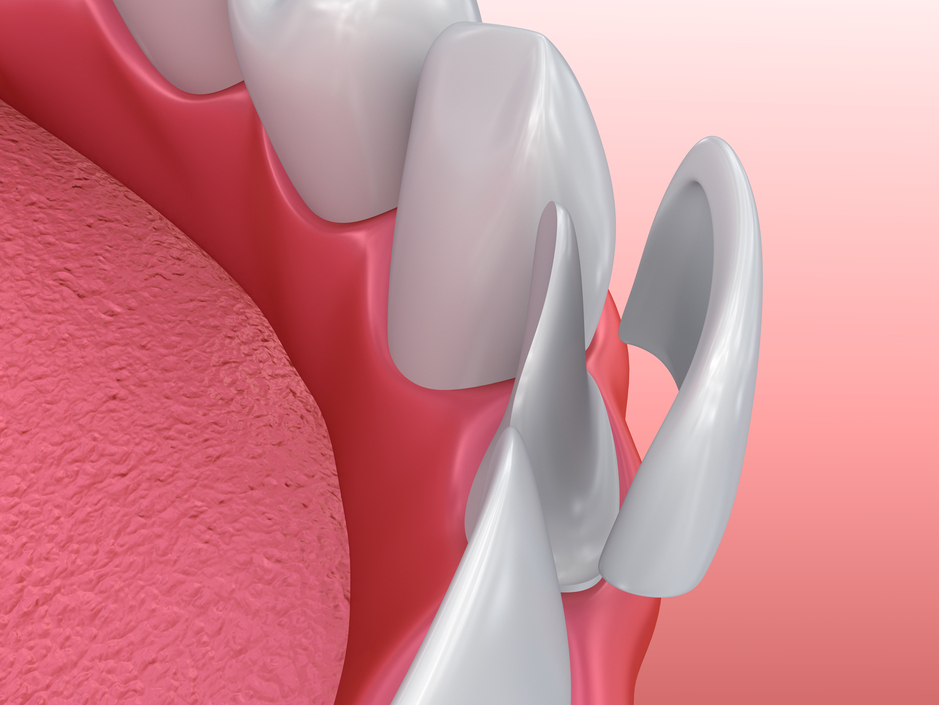

Mặt dán sứ Veneer

Veneer-laminate là những mảnh sứ, Composite hoặc nhựa được dán lên mặt ngoài của răng để tái tạo lại hình dạng và màu sắc của răng như mong muốn